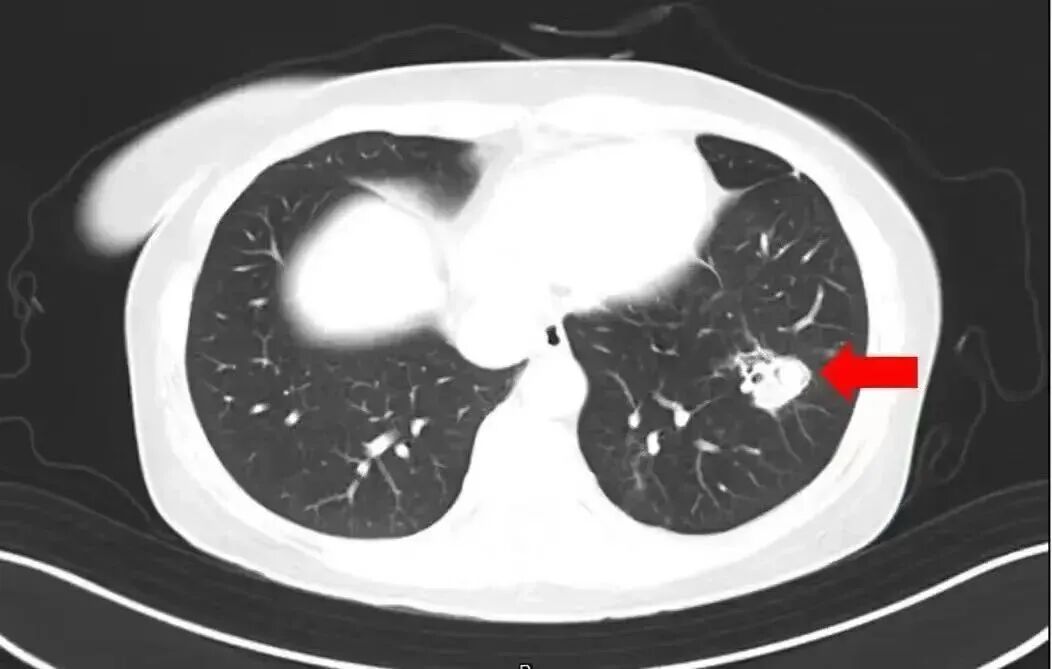

近日,有一条新闻引发网友关注:河南郑州一名6岁女孩跟随家人对老家房子进行清扫,随后就开始持续发烧。经医院检查,发现其脑部被真菌侵蚀出很多个“空洞”。罪魁祸首,就是老房子里霉变粉尘中的“烟曲霉”。

2025年1月,江苏扬州的张大爷为迎接春节开始大扫除,清扫过程中不慎吸入大量灰尘和霉菌孢子,导致哮喘发作。张大爷随即服用了常备的哮喘治疗药物,可症状反而逐渐加重。经检查,张大爷的肺部出现感染,确诊为肺曲霉病。

北京佑安医院感染综合科主任医师李侗曾介绍,对于免疫力低下的人,吸入了这些真菌,就会发病引起肺部的病变——曲霉肺炎。因为它是通过呼吸道感染的,进入血液后可以扩散到全身。大脑因为血供最丰富,所以也是真菌最容易侵犯的器官。